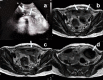

Gossypiboma is a mass of foreign body with cotton matrix accidentally left inside the body after a surgical procedure. It is a surgeon's nightmare and has a varied presentation ranging from asymptomatic cases to the formation of an abscess, mass, intestinal obstruction/perforation, malabsorption, gastrointestinal hemorrhage, and various internal and external fistulization. Genital tract fistulas are one of the most distressing conditions for women of reproductive age that not only hamper their day-to-day work but also impair their social life and psychological state. Colouterine fistula is a rare pathology and has been mainly reported as a complication of diverticulitis in the elderly. We present here a case of gossypiboma presenting as colouterine fistula in a young lady following lower segment cesarean section. The case highlights a rare complication of gossypiboma, probably the first of its kind, and the diagnostic challenges that it presents.